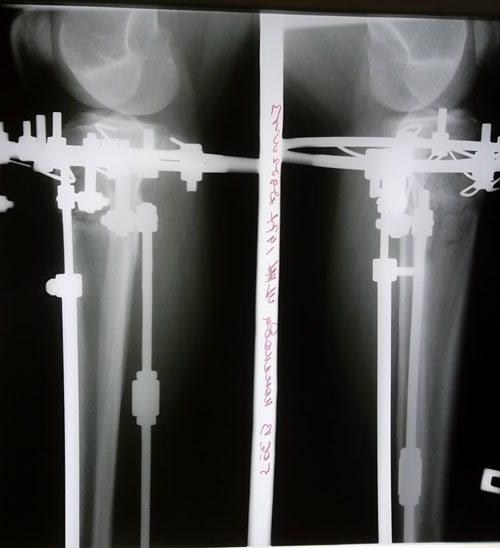

Рентгеновские снимки на 35 - ый день после операции.

Вложения

SAM_5600.JPG

SAM_5599.JPG